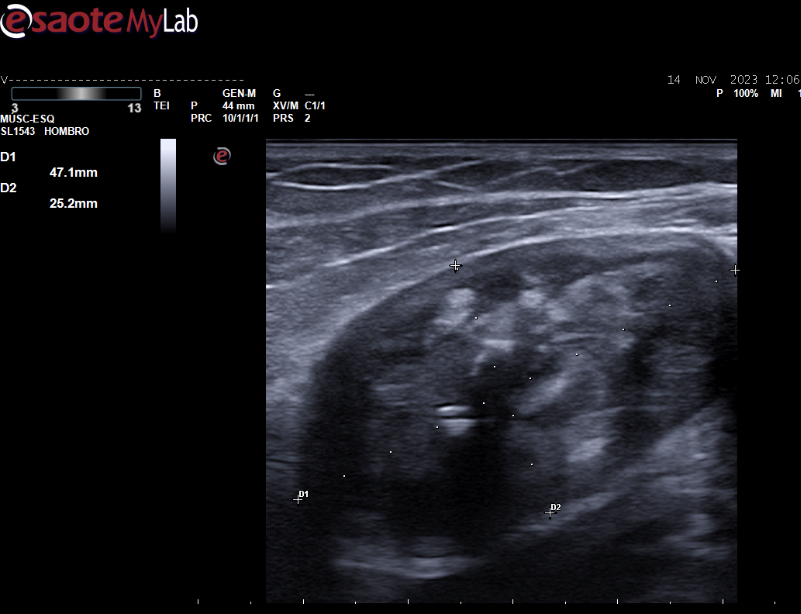

Hallazgos ecográficos

Masa heterogénea de 46*24 mm (zonas hipoecoicas con otras hiperecoicas y zona de microcalcificaciones) con escasa captación Doppler situada superficial al paquete vascular. No se observa lesión quística en la localización teórica del quiste de Baker.

se solicita ecografía reglada a Rayos.